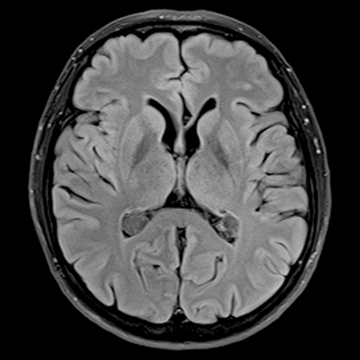

MRI画像例

左右にスクロールして画像をご覧いただけます。

頭部ルーティーン

T2 TSE, matrix 512,

Dark Fluid, matrix 320,